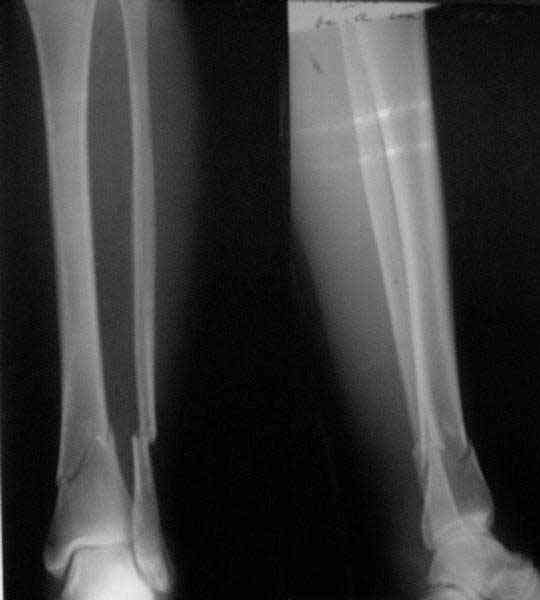

Re: Проксимальный и дистальный переломы tibia

A typical case is attached, also an image with intra-op reduction obtained by a small wire distractor, in the moment of insertion a Poller wire in AP direction. Fixation by a SIGN nail. Despite the fibula was not fixed healing was obtained with the unchanged alignment.